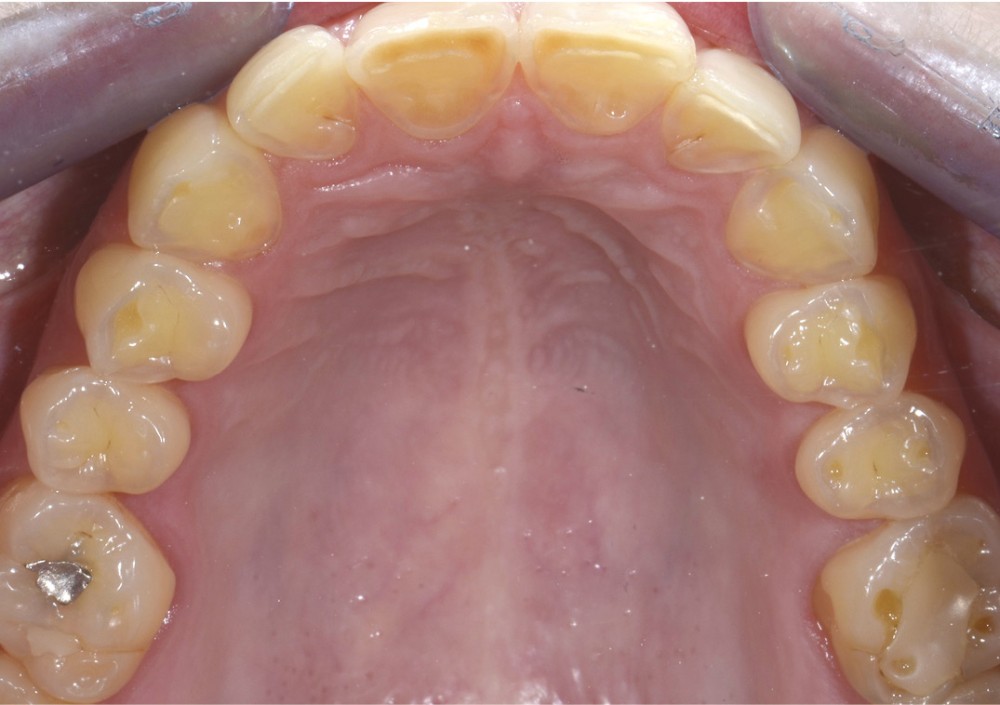

Une patiente âgée de 28 ans se présente en consultation avec une inquiétude au sujet de ses dents postérieures : elle a observé une usure avec un « jaunissement » des faces occlusales et se plaint de sensibilités répétées (fig. 1 à 3).

L’examen général met en évidence un bruxisme nocturne ainsi qu’une consommation peut-être excessive d’agrumes.